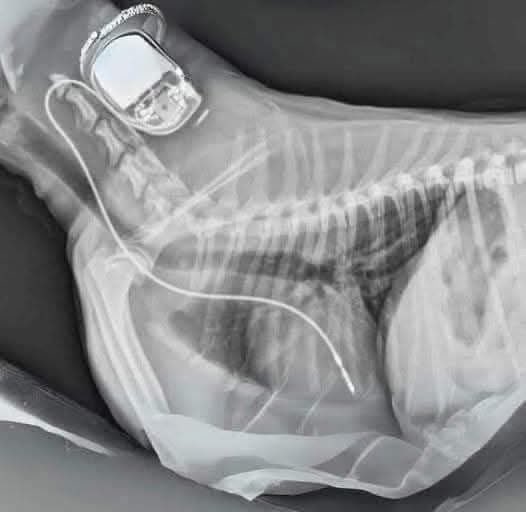

¿Sabías que si tienes un marcapasos, puedes incluirlo en tu testamento para ser donado a un perro necesitado después de tu fallecimiento? Aunque los marcapasos no pueden ser usados para otro humano, pueden ayudar a perros con problemas cardíacos y potencialmente salvar sus

¿Sabías que si tienes un marcapasos, puedes incluirlo en tu testamento para ser donado a un perro necesitado después de tu fallecimiento?

Aunque los marcapasos no pueden ser usados para otro humano, pueden ayudar a perros con problemas cardíacos y potencialmente salvar sus